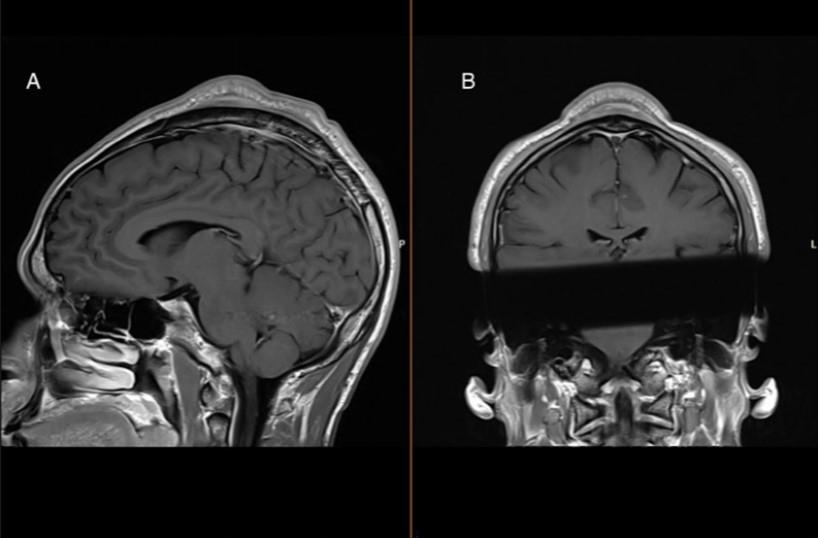

С помощью визуализации была выявлена значительная опухоль под кожей, которую удалили хирургическим путем. Гистологический анализ показал неспецифические изменения, характеризующиеся обширным фиброзом без признаков злокачественности. Примечательно, что уже через месяц после операции пациент не испытывал боли при выступлении и был доволен эстетическим результатом.